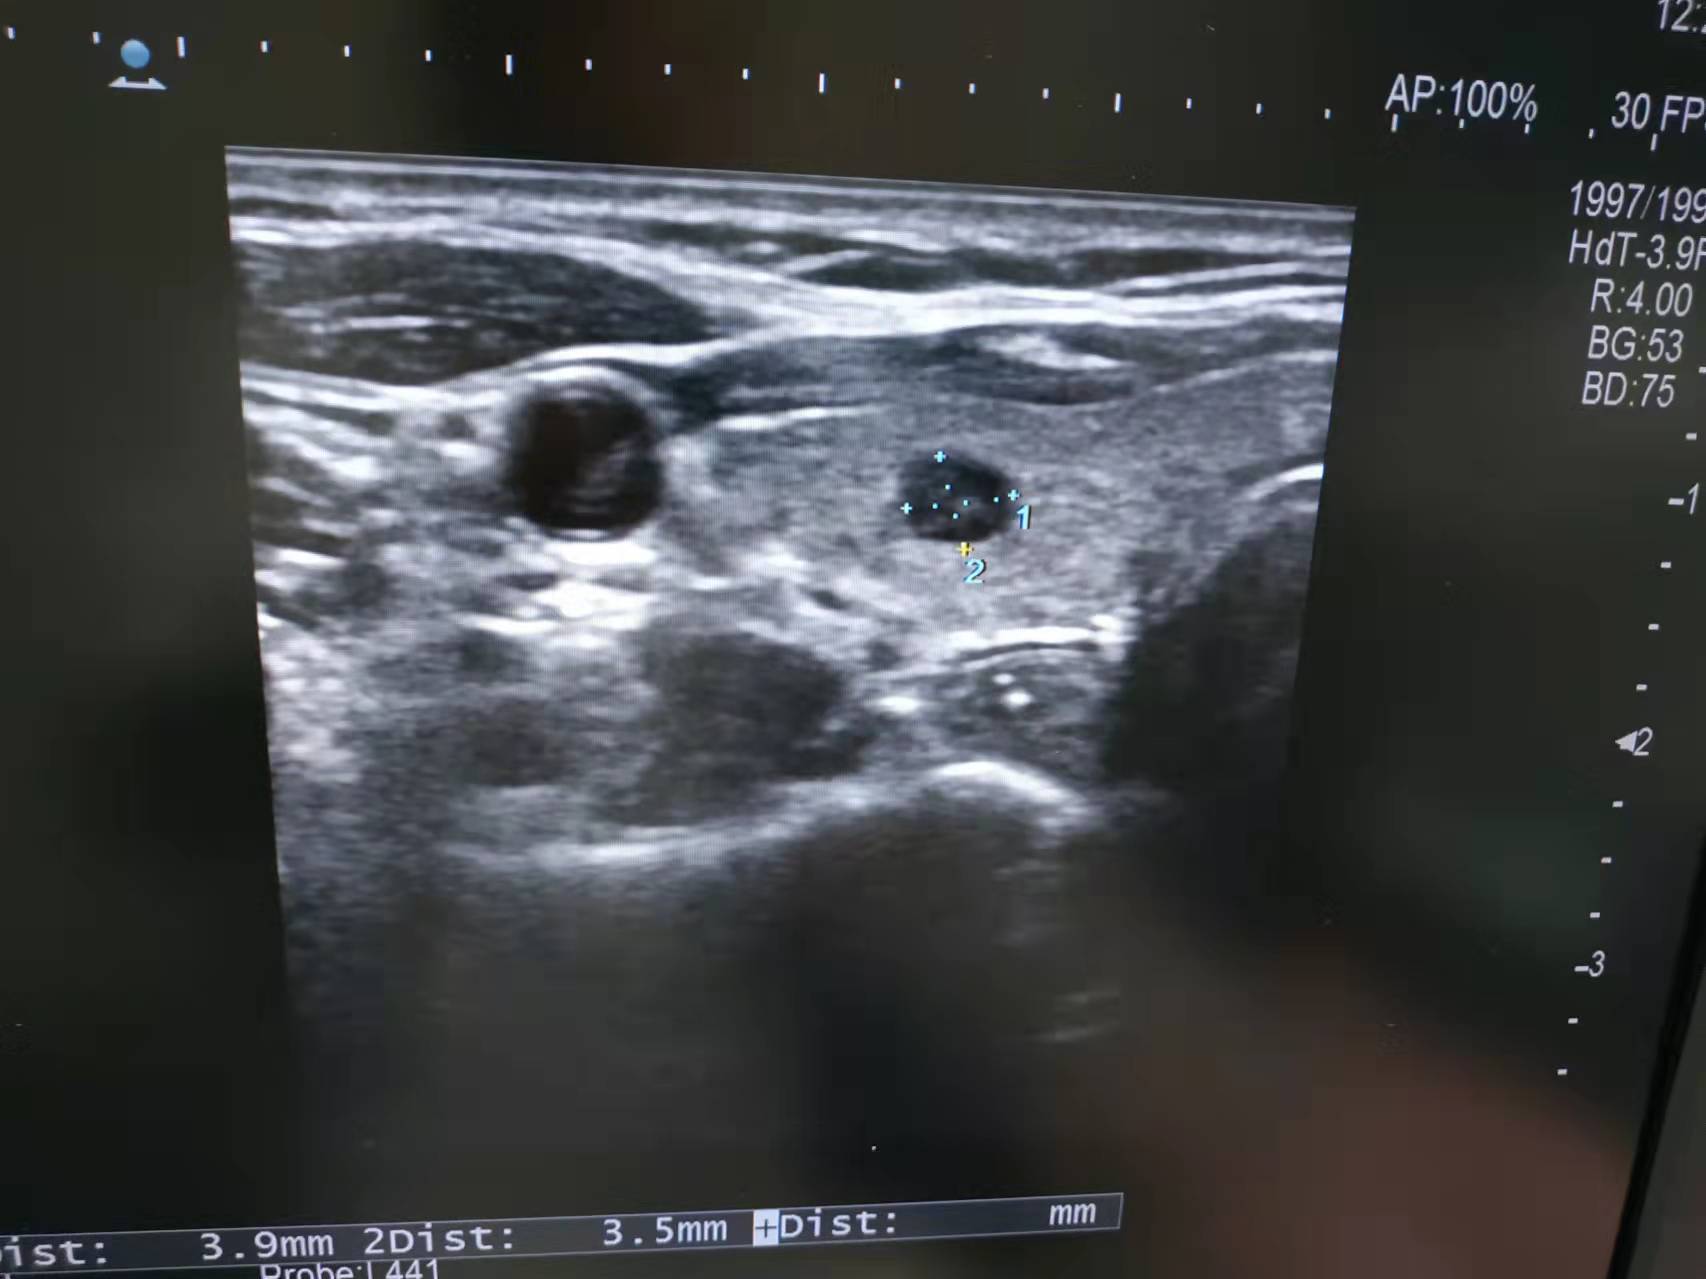

她意外发现左侧甲状腺有一个低回声结节

虽然只有5毫米左右大小

甲状腺超声图

经再次超声复核,医生建议小林在超声引导下做一个甲状腺细针穿刺活检术,通过穿刺取很少的甲状腺结节细胞就可以做病理及基因检查,来明确这个结节是良性的还是恶性的。